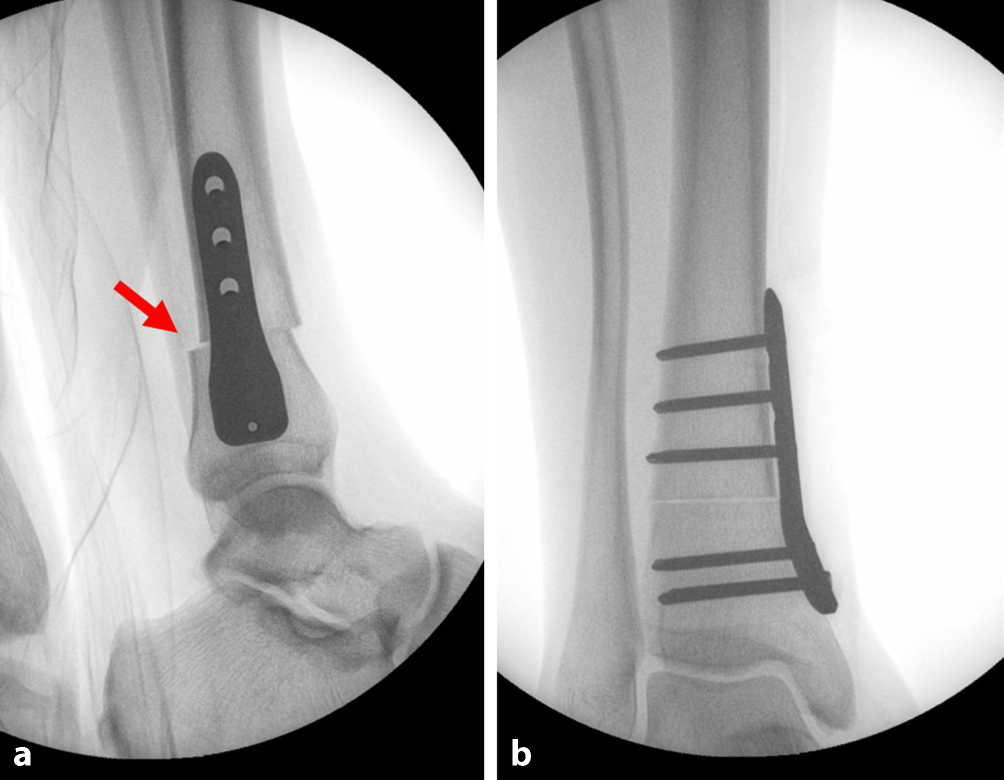

Durch die korrigierende Innendrehung der distalen Tibia kommt es zu einem makroskopisch und radiologisch ersichtlichen leichten a.-p.-Versatz der Tibia distal der Osteotomie, wie in der intraoperativen lateralen Röntgenaufnahme (Abb. 4) zu sehen ist. Dieser entsteht aufgrund der Derotation um das Drehzentrum zwischen Tibia und Fibula bei intakter Membrana interossea und nicht allein um die Tibiaachse und ist in diesem Ausmaß zu tolerieren. Bei pädiatrischen Patienten ist auf eine möglichst schonende Behandlung des Periosts und ggf. Verschluss desselben nach Abschluss der Operation zu achten. Eine grafische Illustration der Prozedur findet sich in Kolp et al. [20].

Abb. 4

a, b Röntgenaufnahmen des oberen Sprunggelenks (OSG) intraoperativ. a Laterale Projektion mit charakteristischem Dorsalversatz der distalen Tibia (roter Pfeil). Aufgrund der Derotation um das Drehzentrum zwischen Tibia und Fibula bei intakter Membrana interossea und nicht allein um die Tibiaachse entsteht ein leichter a.-p.-Versatz, der in diesem Ausmaß zu tolerieren ist. b Anteroposteriore Projektion mit komplettierter Osteotomie und Derotation sowie fixiertem winkelstabilem Implantat. (Mit freundl. Genehmigung, © T. Tondelli et al.)